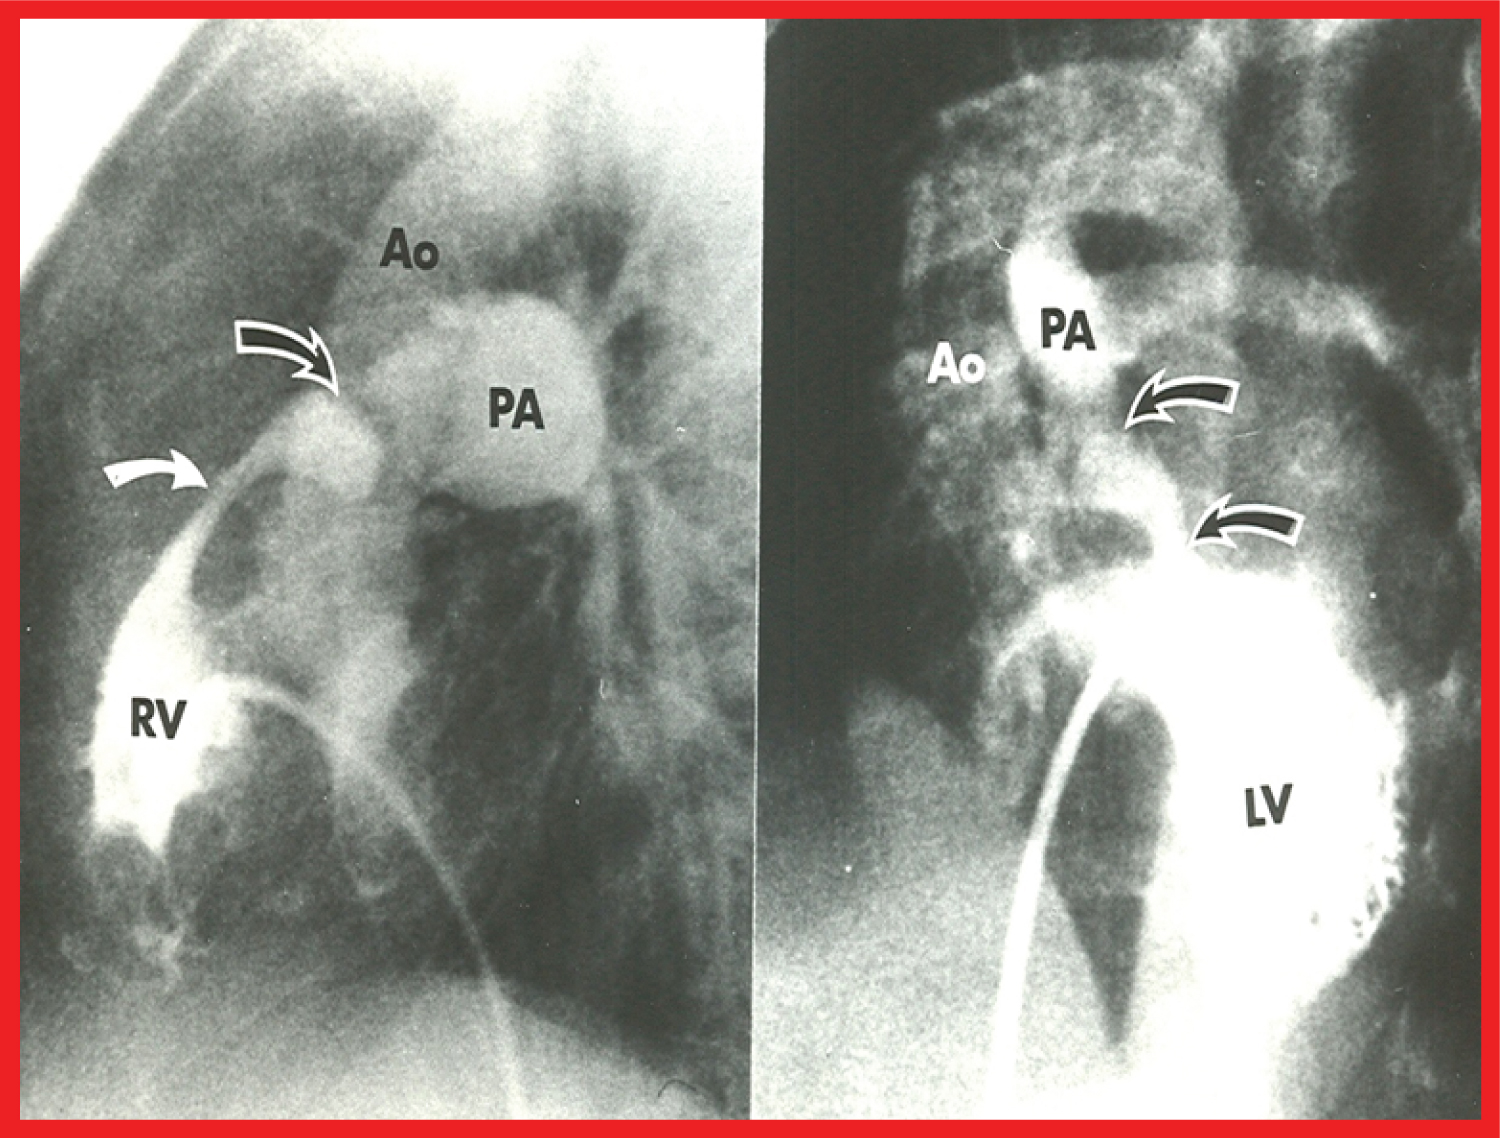

Historical aspects, indications, procedure of BPV, and immediate and follow-up results in patients with pulmonary stenosis associated with cyanotic CHDs were appraised [46-52]. BPV is recommended if the infant/child needs palliation of pulmonary oligemia but is not a candidate for total surgical correction at presentation. The procedure is indicated if the pulmonary valve obstruction is a significant part of the right ventricular outflow tract stenosis and multiple obstructions in series exist (Figure 4) so that there is likely to be residual subvalvar obstruction following relief of valvar narrowing so that flooding of the lungs is prevented. Increase in systemic arterial saturations immediately after BPV and growth of the pulmonary arteries at follow-up (Figure 5) seem to be the benefits of BPV in this subset of patients.

Figure 4: Selected cineangiographic frames from patients with tetralogy of Fallot (left) and d-transposition of the great arteries (right), demonstrating two sites of pulmonary outflow obstruction (two arrows). When the pulmonary valve obstruction is relieved by balloon valvuloplasty, the subvalvar obstruction remains and prevents the flooding of the lungs [48].

Ao: Aorta; LV: Left Ventricle; PA: Pulmonary Artery; RV: Right Ventricle View Figure 4

Figure 5: A) Selected frames from pulmonary artery cineangiograms in a sitting-up view in a patient with tetralogy of Fallot, prior to and B) 12 months following balloon pulmonary valvuloplasty. Note the significant improvement in the size of the valve annulus and main pulmonary artery (MPA) at follow-up [48].

LPA: Left Pulmonary Artery; RPA: Right Pulmonary Artery View Figure 5